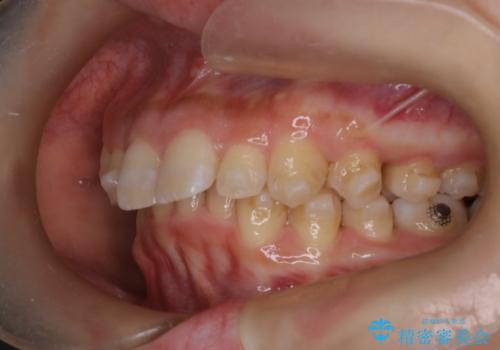

- 上の前歯の出っ歯と前歯の深い咬み合わせを治したいとのことで来院された患者様です。

上顎の歯は後方移動とIPR(歯と歯の間を削る)によって口元が引っ込むように、下顎は歯列全体の拡大とIPRによって上顎とバランスよく咬み合うように設計し、インビザラインにより治療を行うこととしました。

上顎歯列の後方への移動量が多く、右側の奥歯の咬み合わせを改善する必要もあったため、治療には長期間を要しました。